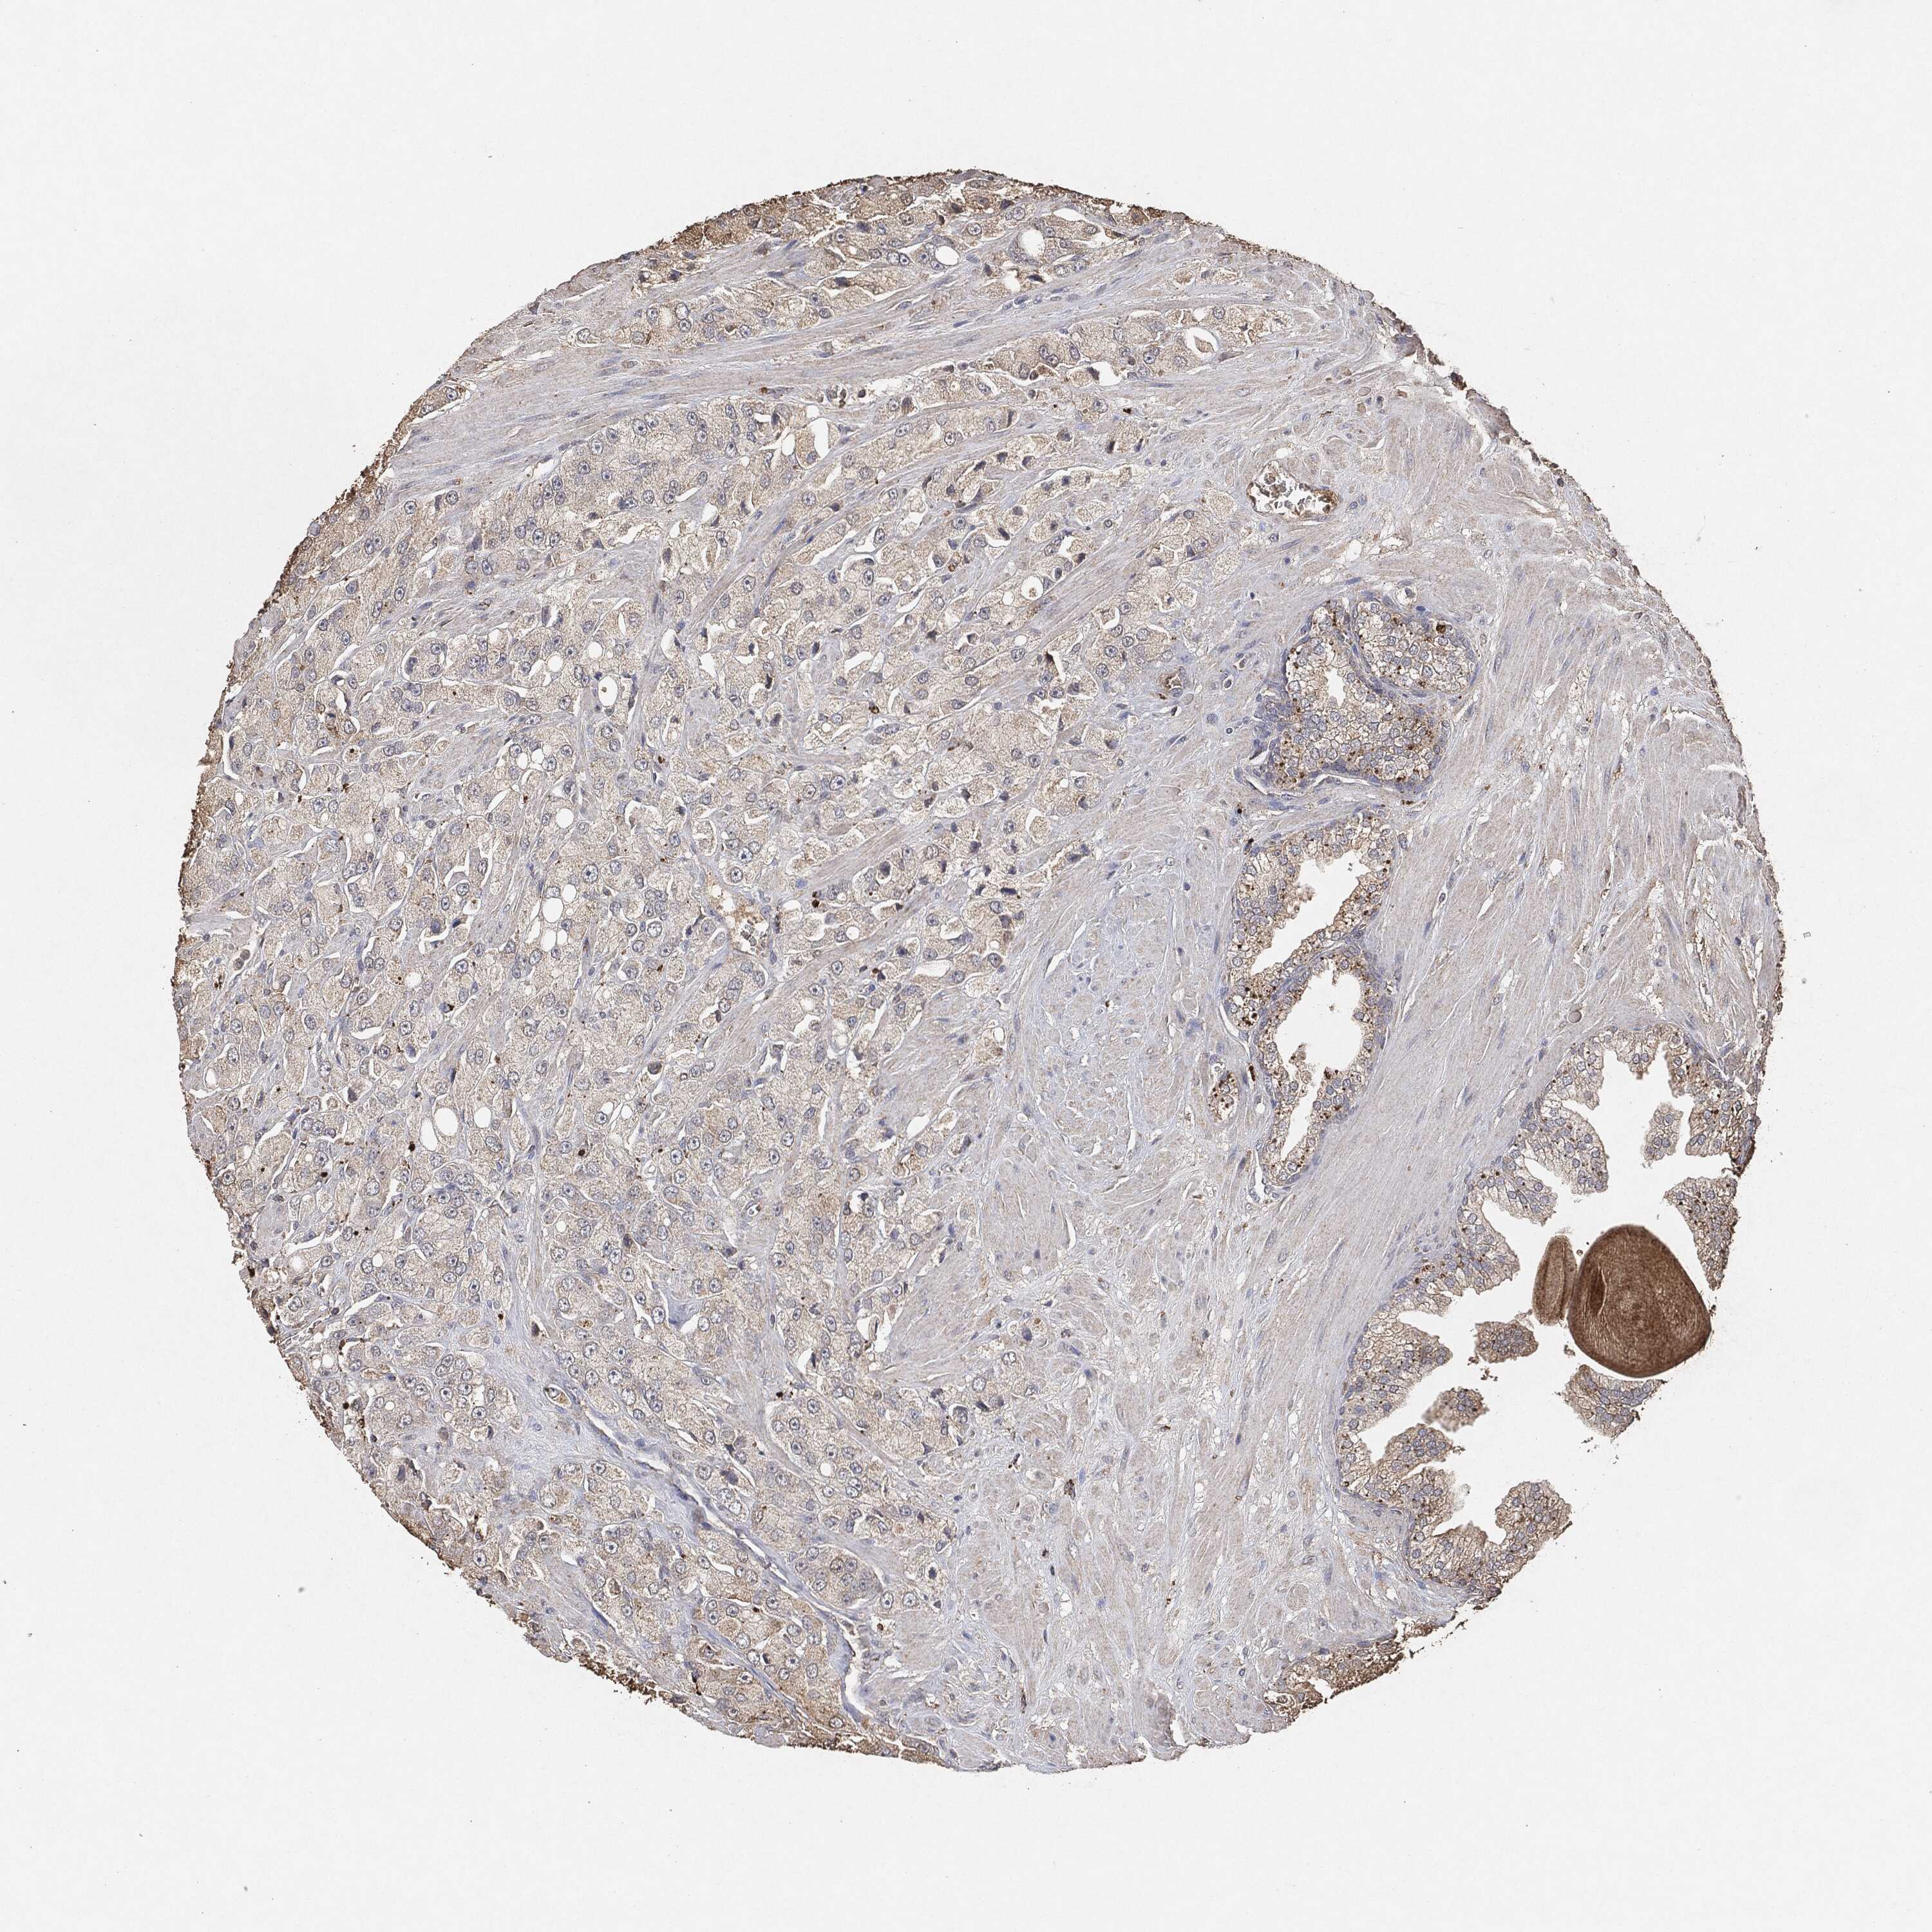

PROSTATE CANCER - Protein expressioni

A mouse-over function shows sample information and annotation data. Click on an image to view it in a full screen mode. Samples can be filtered based on level of antibody staining by selecting one or several of the following categories: high, medium, low and not detected. The assay and annotation is described here.

Note that samples used for immunohistochemistry by the Human Protein Atlas do not correspond to samples in the TCGA dataset.

Antibody stainingi

Antibody staining in the annotated cell types in the current human tissue is reported as not detected, low, medium, or high, based on conventional immunohistochemistry profiling in selected tissues. This score is based on the combination of the staining intensity and fraction of stained cells.

Each image is clickable and will lead to virtual microscopy that enables deeper exploration of all samples and also displays staining intensity scores, fraction scores and subcellular localization as well as patient and tissue information for each sample.

Adenocarcinoma, Medium grade

Adenocarcinoma, Low grade

Adenocarcinoma, High grade

Adenocarcinoma, NOS